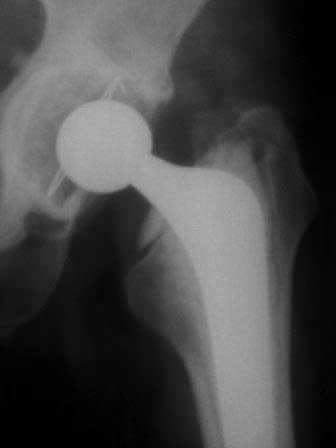

В дополнение к моему вышеуказанному пациенту. Досылаю послеоперационный снимок, который я не выслал сразу.

На заключительных снимках явная нестабильность чашки и вероятная ножки, возможно на повторный прием придет не столь радостный (пессимистический прогноз) надеюсь, что все будет по-другому

Нет вы не поняли! Вы поспешили с выводом! Я не смог выслать окончательный, послеоперационный снимок, по техническим причинам. Я это сделал позже, что Вы и видите ниже! Извините, если я Вас запутал!

С последним, третьим снимком он ко мне и обратился, после чего он был и прооперирован на правом тазобедренном суставе!